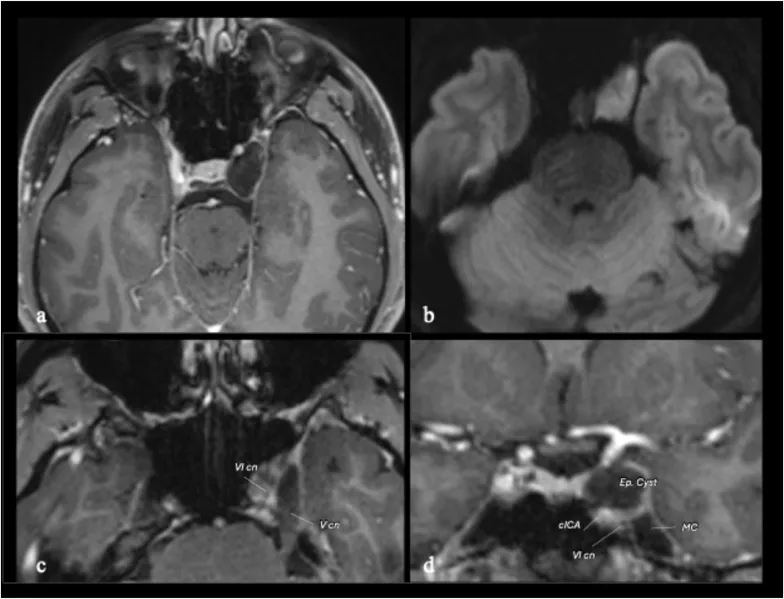

图1:术前轴位磁共振成像显示,病变位于海绵窦上外侧隔腔,T1加权图像呈低信号且无对比增强,弥散加权成像显示明显弥散受限,这些发现高度提示为表皮样囊肿。轴位和冠状位T1加权增强图像显示,外展神经相对于颈内动脉海绵窦段向下外侧移位。Meckel腔未受表皮样囊肿侵犯。

鉴于临床症状持续恶化,手术干预被提上日程,主要治疗目标为减压动眼神经。基于病变位于海绵窦的上外侧及上部区域,并导致颈内动脉向内侧移位、颅神经向外侧移位(图1、2),最终选择了对侧单鼻孔内镜经鼻入路(图3)。选择此技术旨在最小化手术通道、避免牵拉脑组织、降低总体手术并发症,同时允许直接抵达病灶以实现动眼神经减压。